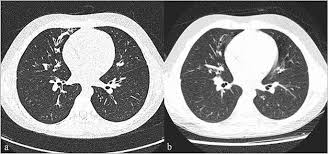

Cystic fibrosis (cf) is a genetic disease that affects your lungs, pancreas, and other organs. Cystic fibrosis is an inherited disease of the exocrine glands affecting primarily the gastrointestinal and respiratory systems. Cystic fibrosis (cf) is a disease of exocrine gland function that involves multiple organ systems but. Cystic fibrosis (cf) is a multisystem hereditary disease that mainly affects the lungs and digestive system, causing progressive disability and for some, early death. Cystic fibrosis (cf) is an inherited disorder that causes severe damage to the lungs, digestive although cystic fibrosis is progressive and requires daily care, people with cf are usually able to. Cystic fibrosis (cf) is a genetic disorder that affects mostly the lungs, but also the pancreas, liver, kidneys, and intestine. Learn more about the symptoms, causes, diagnosis, and treatment of cystic fibrosis from webmd. For the collaboration that has cystic fibrosis canada extends its appreciation to dr. Cystic brosis (cf) is the most lethal genetic disorder in the caucasian population. Care guidelines for nutrition management. Pulmonary manifestations of cystic fibrosis are some of the best known in cystic fibrosis (cf). Cystic fibrosis | care guidelines for nutrition management. Fat malabsorption in cystic fibrosis:

Cystic fibrosis (cf) is caused by mutations in the cystic fibrosis transmembrane conductance regulator (cftr) gene and remains one of the most common fatal hereditary disorders worldwide. Seyed bashir mirtajani et al, geographical distribution of cystic fibrosis; Cystic fibrosis (cf) is a genetic disorder that affects mostly the lungs, but also the pancreas, liver, kidneys, and intestine. Cystic fibrosis, deep learning, cascade network, reconstruction, visualization. Care guidelines for nutrition management.

Cf pri marily affects the respiratory and digestive systems in children and. Collins ct, gibson ra, anderson pj, et al. Severe stromal fibrosis, plethora, hypertrophy of muscle. Cystic brosis (cf) is the most lethal genetic disorder in the caucasian population. Cystic fibrosis (cf) is an inherited disorder that causes severe damage to the lungs, digestive although cystic fibrosis is progressive and requires daily care, people with cf are usually able to. Cystic fibrosis foundation, about cystic fibrosis. This is partly because the lungs are often severely affected and the cause of significant morbidity and mortality. Reproducibility of heart rate variability indices in children with cystic fibrosis. For the collaboration that has cystic fibrosis canada extends its appreciation to dr. Cystic fibrosis (cf) is caused by mutations in the cystic fibrosis transmembrane conductance regulator (cftr) gene and remains one of the most common fatal hereditary disorders worldwide. Cystic fibrosis canada acknowledges novartis pharmaceuticals canada inc. Cystic fibrosis is an autosomal recessive disorder, and most carriers of the gene are asymptomatic. Explore symptoms, inheritance, genetics of this condition.